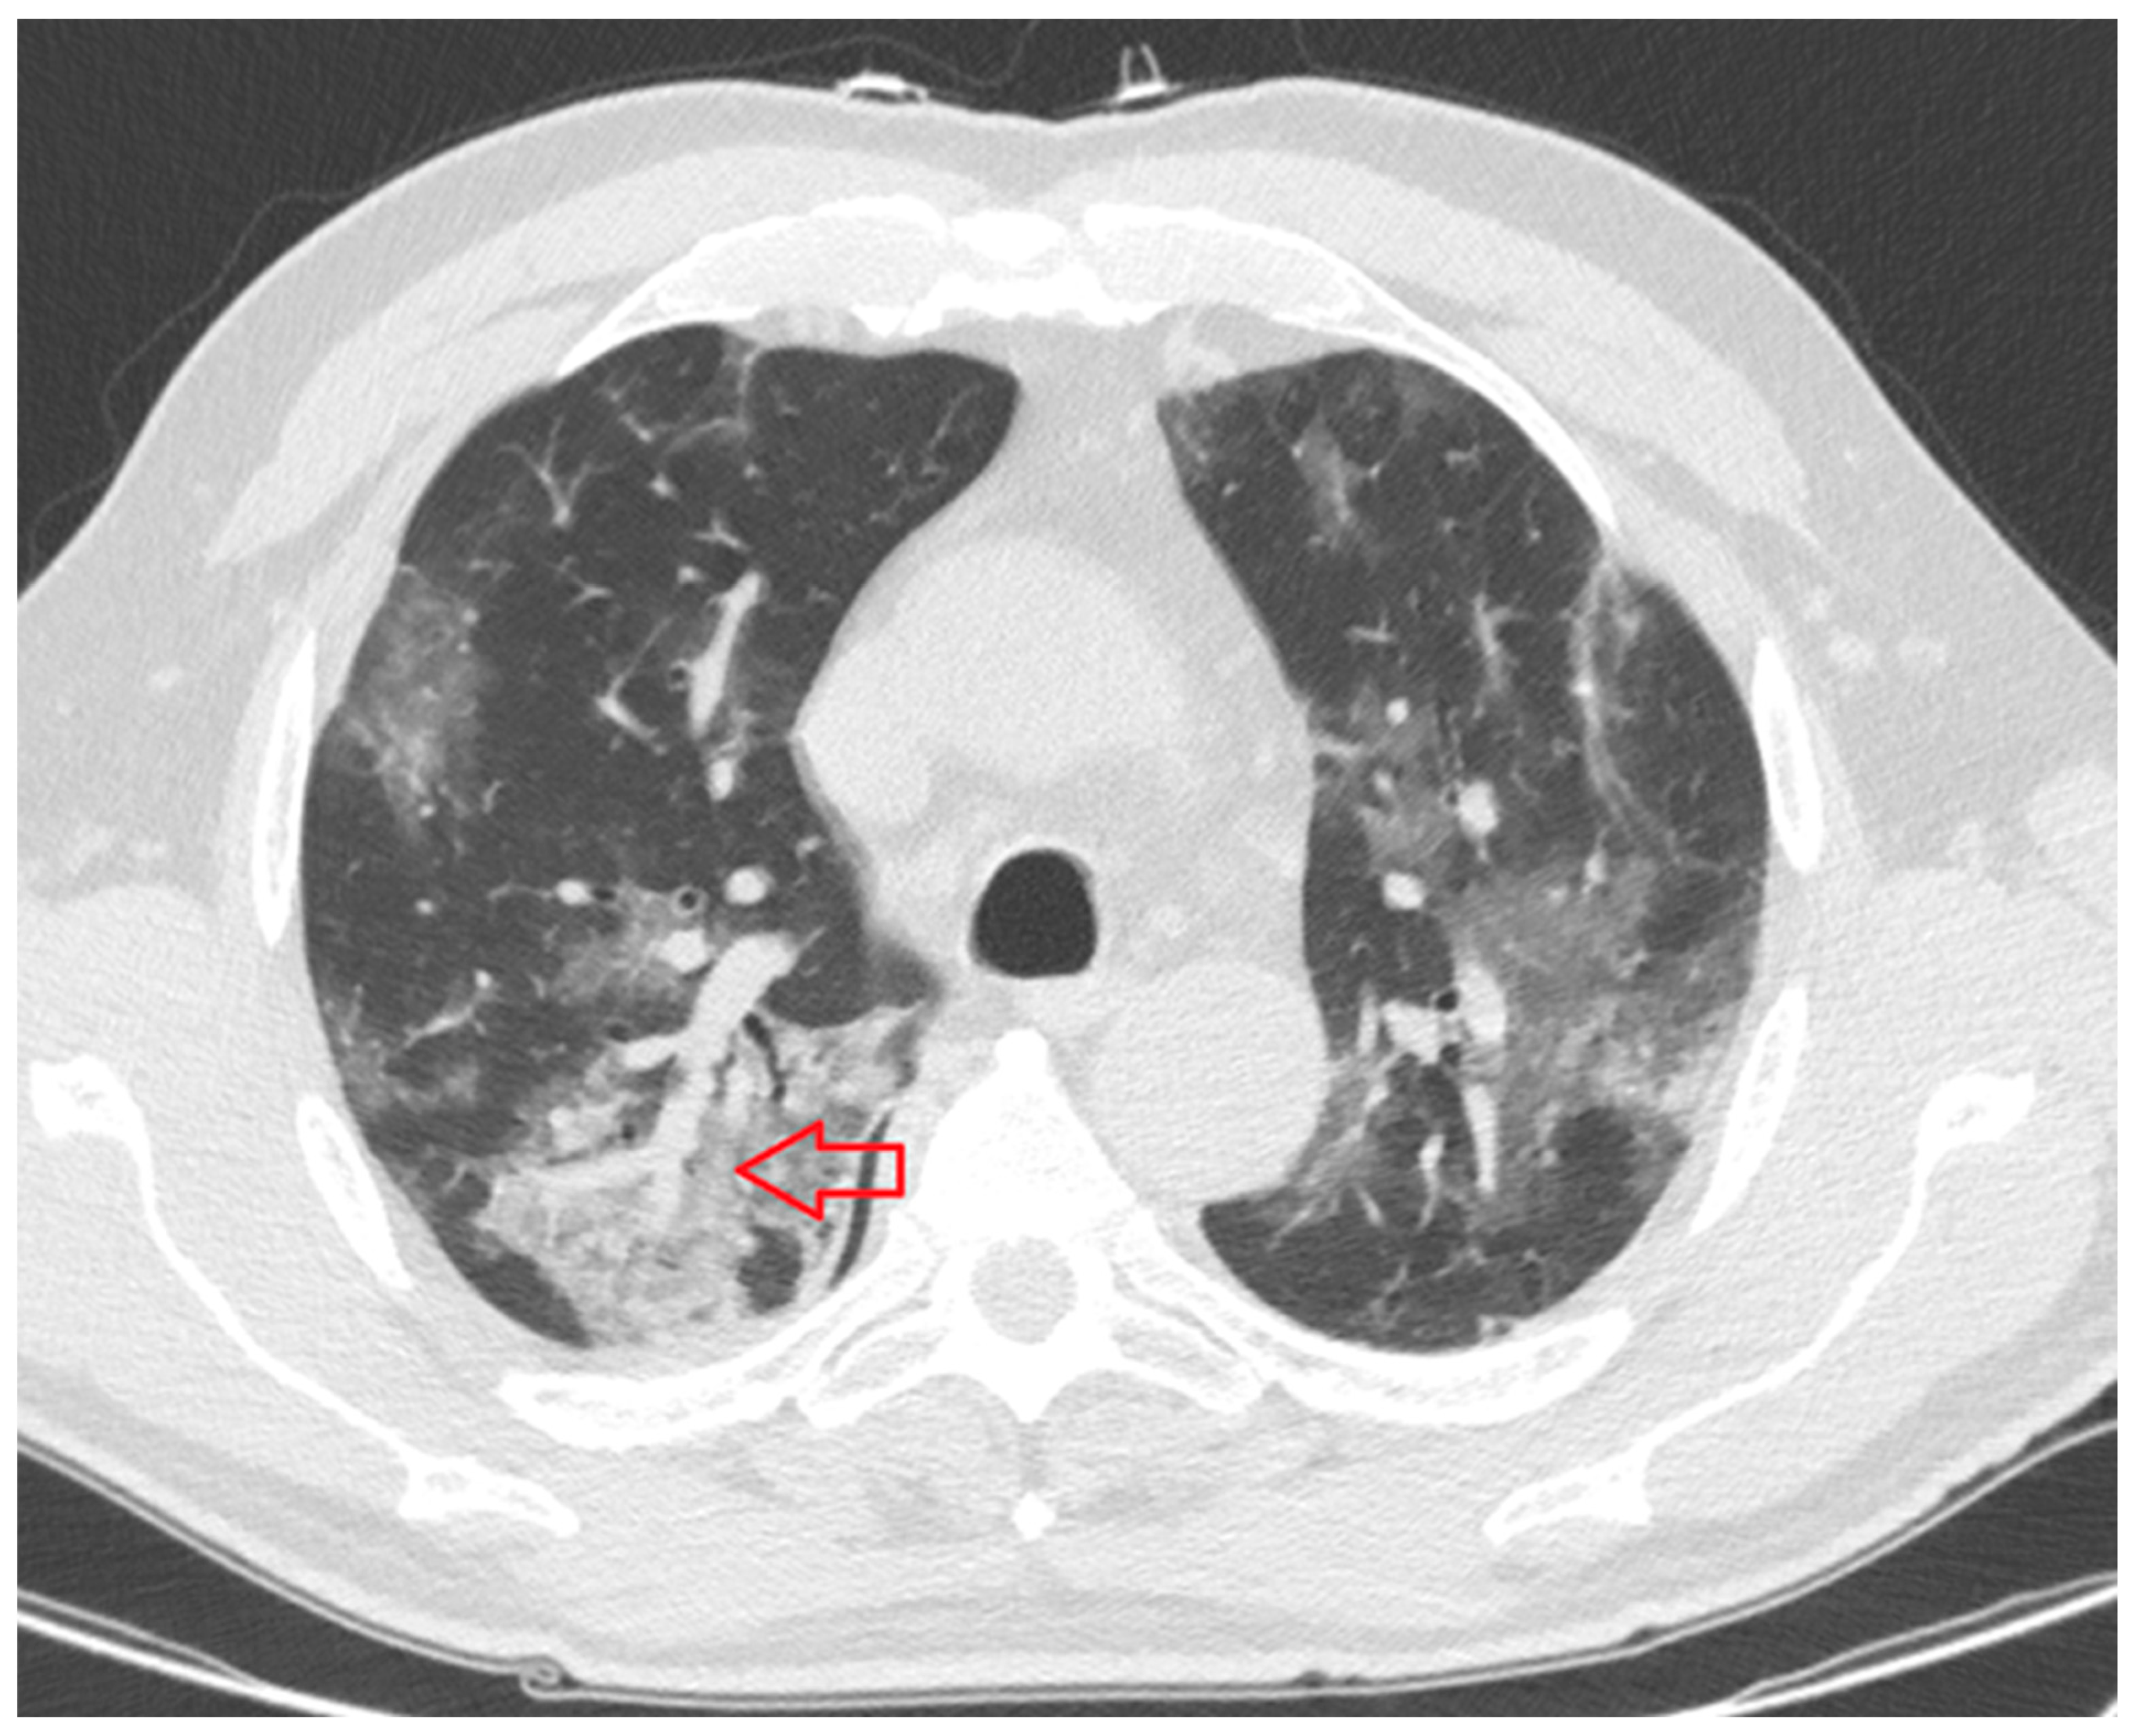

- Consolidation: homogeneous increase in lung parenchymal opacity obscuring the vascular margins and airway walls with an air bronchogram (pattern of air-filled bronchi on a background of opaque airless lung) (Figure 3);